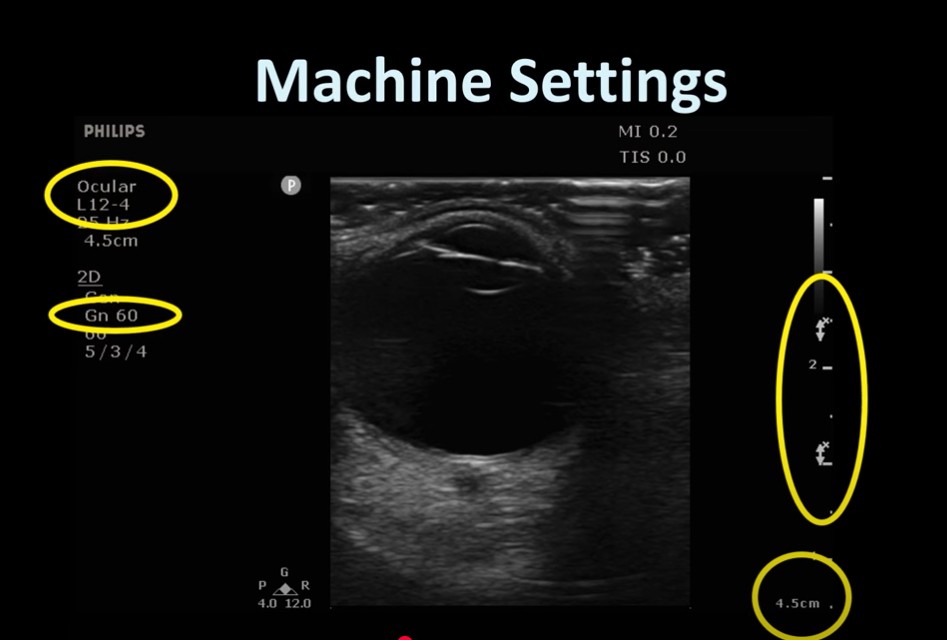

Apr 25, 2025 Guardians of the Sound2:263:554:025:29 Very important to anchor your arm on the shoulder [see right picture] to avoid putting any pressure on the globe]. Review transcript on YouTube 5:39 – 6:166:277:16 In both views the patient is asked to look right and left and up and down.7:367:56 You need an ophthalmology setting on your machine so that you don’t exceed the safe TI and MI.8:018:328:459:029:119:5710:2910:3610:4010:4511:1211:3511:5012:4013:05 Warning Use only eye settings. Don’t use the MSK setting in the picture below: